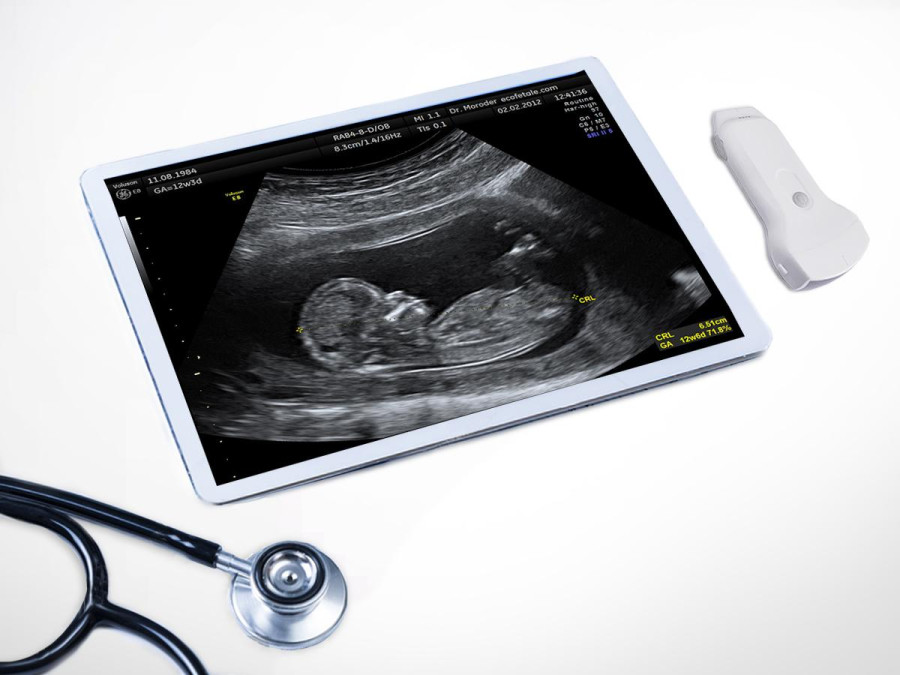

Ultrasonography (USG), or ultrasound, is a widely used clinical imaging system for quick diagnosis and treatment. Allowing doctors to see images of organs inside the human body, ultrasound helps doctors diagnose various diseases, traumatic injuries, fetal development, and abnormalities in pregnancy. The advantage of ultrasound is that, unlike X-ray imaging, it does not emit harmful ionising radiation. It relies on sound waves to create images and is safer in comparison. Patients and medical practitioners are not exposed to radiation while using this device. It is also a non-invasive and painless diagnostic technology. There has been considerable interest in using this technology as it requires very little infrastructure, training, and maintenance compared to other imaging systems. Nevertheless, ultrasound has not seen widespread use in developing countries due to the high cost of the machine.

The advances in hardware and software have made ultrasound devices more compact, affordable, and easier to use, with good image quality and performance. Pocket-sized, handheld ultrasound devices first appeared on the market in the late 1990s. Since then, they have been upgraded numerous times to provide better performance and image quality. These handheld ultrasound devices are cheaper and cost less than one-fifth of the price of conventional cart-based ultrasound machines. The low cost of these ultrasounds has made them popular worldwide, and physicians use them as point-of-care ultrasound (PoCUS) in hospitals and clinics.

Handheld ultrasound is a lightweight, compact, and portable form of ultrasound technology. It easily fits into physicians’ pockets and saves time in emergencies. It also allows physicians to get first-hand information about patients, and then refer them for a standard ultrasound test based on the pre-diagnosis report. Due to the inherent advantages of handheld ultrasound devices, physicians have been using them as pre-diagnostic tools, just like a stethoscope. Recognising the usefulness of handheld ultrasound, the International Medical Community has also started referring to it as an e-stethoscope. Handheld ultrasound as an e-stethoscope could usher in a new era in the healthcare sector. It would arm physicians with quick, easy, and harmless means of visually observing the ecosystem of internal organs functioning in real-time to provide a more accurate diagnosis.